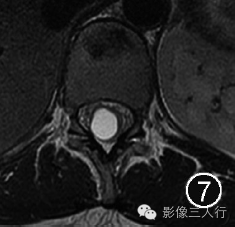

图4~7 男,45岁。腰椎MRI显示第五脑室是位于脊髓圆锥内且囊壁光滑的囊腔,囊腔内的脑脊液在矢状面T1WI上呈低信号(图4),在横断面T1WI上呈低信号(图5),在矢状面T2WI上呈高信号(图6),在横断面T2WI上呈高信号(图7)。所有图片均由加拿大渥太华大学渥太华医院Carlos Torres教授提供